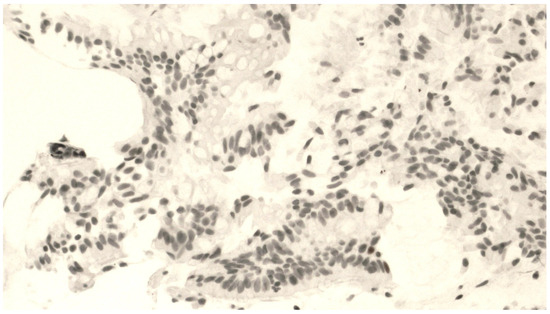

The mean number of vimentin+ cells was 21.8 ± 9.5 cells. Figure 2 shows a representative staining of bronchial biopsies for vimentin expression. In Figure 3, it is reported that a control of immunohistochemical staining omitted the primary antibody and was documented by the absence of staining.

Figure 2.

Fragment of bronchial mucosa immunohistochemically stained by an anti-vimentin antibody. The presence of an epithelial–mesenchymal transition is shown by a number of positive cells distributed inside the epithelium at 400× magnification.

Figure 3.

Control of immunohistochemical staining omitting the primary antibody: absence of staining at 400× magnification.

In contrast to p63, we found a positive correlation between FEV1% predicted and vimentin expression (r = 0.670; p = 0.008; Figure S3), whereas no significant correlation was observed between vimentin+ cells and FEV1 when the latter was expressed in liters (r = 0.13 and p = 0.64; Figure S4). Similarly, there were no discernible differences in vimentin expression between COPD and non-COPD patients (Table 3). No difference was found between emphysematous and non-emphysematous patients (21.65 ± 10.96 vs. 20.71 ± 6.73, respectively, p = 0.80).

Finally, in marked contrast with p63, vimentin expression was more prevalent in the more distal areas (lobar and segmental bronchi) compared to the more proximal ones (=0.042; Table 3).